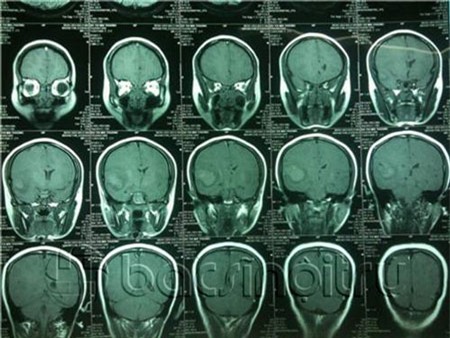

Tình trạng bệnh của sản phụ Đỗ Thị Mai Thương. |

Lại

được chuyển tiếp về khoa thần kinh, bác sĩ tại khoa này cho tôi biết:

“Những trường hợp này khó quá bởi nhìn trên phim chụp không thể phát

hiện máu chảy từ đâu để xử lý. Nhất là lúc này sản phụ lại có bầu, nếu

Từ

những thông tin ban đầu này chúng tôi đã có có một số định hướng chẩn

đoán rằng bệnh nhân bị đột quỵ não bao gồm xuất huyết dưới nhện hoặc

xuất huyết não. Viêm màng não hoặc viêm não.

Vì

bệnh nhân có thai, chúng tôi đã cân nhắc chọc dịch não tủy trước và cho

kết quả: Dịch não tủy hồng đều cả 3 ống xét nghệm và để không đông (sau

6 giờ). Sau đó để có chẩn đoán chính xác và an toàn cho thai nhi, y bác

sĩ khoa cấp cứu đã quyết định chụp MRI sọ não và mạch não kết luận:

Hình ảnh khối dạng máu tụ thùy thái dương phải. Sau khi làm việc với gia

đình sản phụ, báo cáo tình hình, chúng tôi tiến hành ca mổ”.